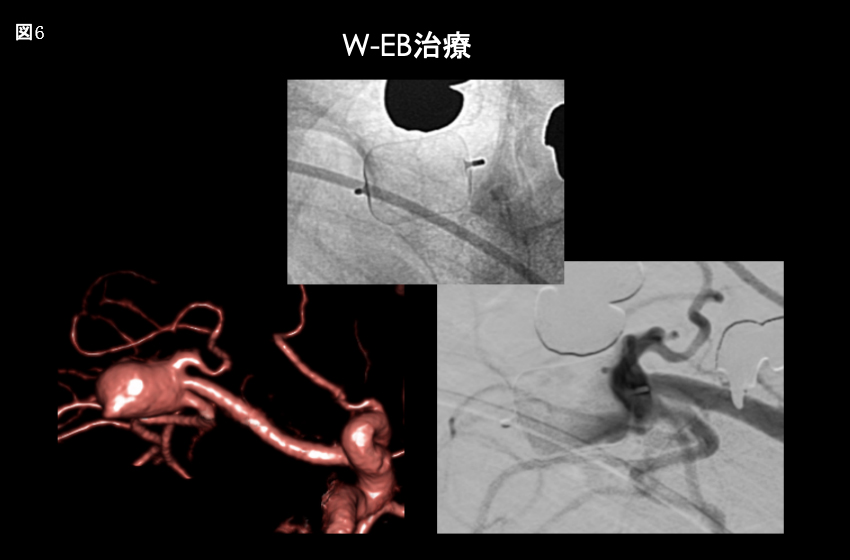

新たな脳動脈瘤治療 W-EB

W-EBとは脳動脈瘤内の空隙を埋めるように展開、留置することで動脈瘤内への血液流入を阻害し、瘤内の血栓化を促す。その治療原理はフローダイバーターと同様であり、単位面積あたりの金属被覆率はフローダイバーターより高く有効性、安全性は高い。

図6:右大型中大脳動脈瘤に対するW-EB留置術。留置後動脈瘤内の血流が停滞している。